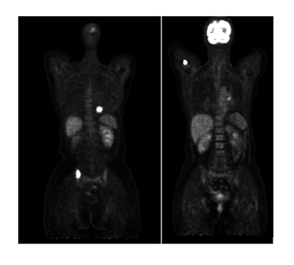

Our patient was a 65-year-old female diagnosed with Grade III ER-/PR-/Her-2 invasive ductal carcinoma in the left breast. She underwent neoadjuvant chemotherapy, followed by left mastectomy and radiotherapy. Six months after completion of therapy, the patient presented for a routine clinical evaluation and underwent a follow-up 18F-FDG PET/CT examination. At the time of referral, the patient reported mild persistent pain in the right upper limb, without a history of trauma. The laboratory tests showed normal platelet counts, hemoglobine and white blood cells, mild elevation of alkaline phosphatase. In addition, tumor marker CA 15-3 was above the normal refrence range 68U/mL, while CEA was normal. Liver and renal function test were within the normal limits. The 18F-FDG PET/CT images identified two focal areas of increased radiotracer uptake in the right iliac bone and the right femoral bone, both without noticable structural abnormalities on the CT. There were considered metabolically active but CT-negative bone lesions. Furthermore, a focal FDG-avid pulmonary lesion was detected, suspicious for lung metastases.